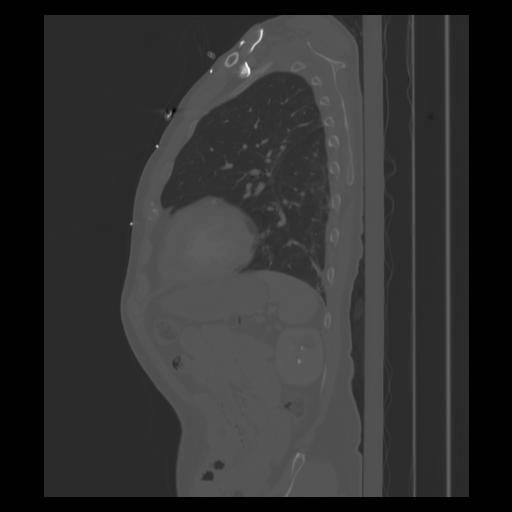

30 CUERPO,CE,Sagittal,3.000,CUERPO,Sagittal,